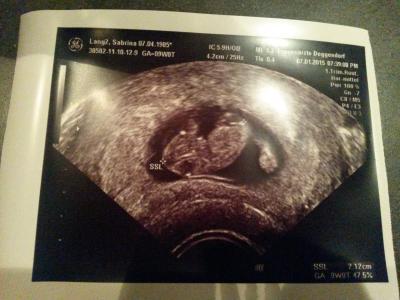

Hi Mamis..... Eine Frage an die die schon ein Kind haben. Geht ihr wieder zu einem Geburtsvorbereitungskurs? Hier noch ein Bild vom FA-Besuch gestern. Alles supi :-)

Bild zu Geburtsvorbereitungskurs beim 2. Baby und ein Bild unseres Gummibärchens :-) - Forum für August - Mamis